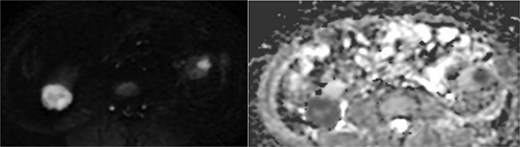

Abdominal magnetic resonance imaging (MRI) showed approximately seven to eight right renal masses (largest 32 × 35 × 37 mm) and five to six left renal masses (largest 62 × 55 × 55 mm). The renal lesions were iso- to mildly hypointense on T1-weighted imaging and mildly hypointense on T2-weighted imaging, without macroscopic fat. Post-gadolinium images demonstrated heterogeneous enhancement with central necrosis in the dominant masses (Fig. 3). Diffusion-weighted imaging showed marked restriction in the viable tumor components (Fig. 4). The dominant left renal mass, located in the mid kidney, demonstrated invasion of the posterior renal fascia. Subacute hemorrhage under the left renal capsule measured up to 24 mm in thickness.

Diffusion-weighted imaging (b = 800) and ADC maps showing restricted diffusion in the viable components of bilateral renal tumors.